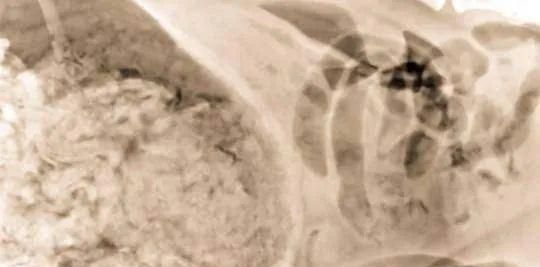

医生给Harvey拍了X光片后发现,这家伙的肚子里竟然装了满满一肚子的袜子。